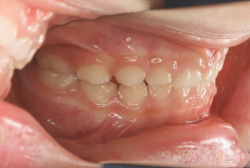

上顎前突

上顎前突(出っ歯)とは上顎が前に出ている状態です。この症状の特徴は、上下の歯並び全体の位置関係が相対的に上顎が優位になっていて、前歯が外に反っているだけでなく奥歯の位置関係も上が前にズレています。さらに凸凹の症状も合併していることがよくあり、上の前歯の見た目を気にして来院する方が多いのですが、実は今言った理由で噛み合わせにも異常があるため、このまま放置すると顎関節症という症状が出ることもあります。

「出っ歯を治したい」という主訴で来院したケースです。診断の結果、「2級1類の上顎前突+軽度叢生」と判明しました。2級というのは、基本的に出っ歯の噛み合わせになっていることを言います。その中でも上の前歯が著しく外に反っているケースを、「1類」といいます。初診時の横向きの写真を見ると、それがはっきり分かります。上の前歯に押されて唇も膨らんで、審美線をかなりオーバーしています(審美線とは、鼻の先端と顎の先端を結ぶ線のことで、この線よりも唇は内側にある方が良いとされています)。

このような症状の場合は、前歯を内側に入れるためにかなり大量の隙間を必要とします。通常は上下左右の小臼歯を抜歯させていただくのが正解です。治療後は歯の角度が正しくなっただけでなく、唇の審美性が大幅に改善しました。もちろん噛み合わせ的にも正しい状態が確立しています。